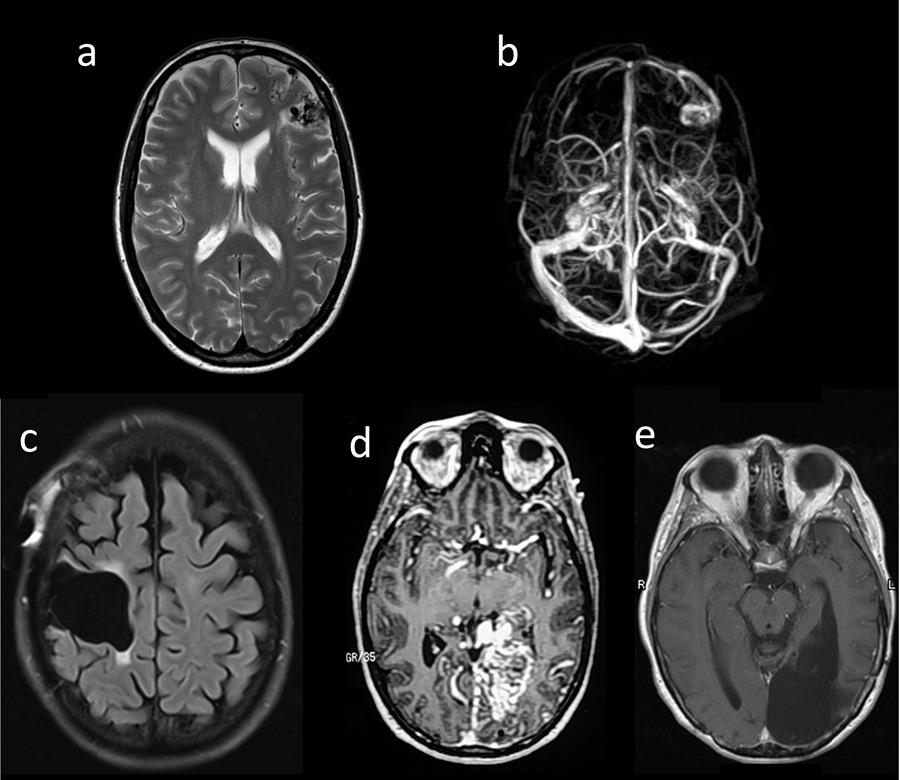

Figure 1

(a, b) Patient 1: T1-MRI (magnetic resonance imaging ) (a) and MRI-venogram (b); (c) Patient 2: MRI (FLAIR) after surgery; (d, e) Patient 3: MRI-angiography prior to surgery (d) and MRI (T1) after surgery (e).

A 34-year-old woman developed a secondarily generalised epileptic seizure and was diagnosed with an AVM with perinidal angiogenesis in the left middle frontal gyrus. Two partial embolisations were performed: one shortly thereafter and another 19 years later (fig. 1a, b). At the age of 54, she developed bulbar onset ALS meeting the criteria for definitive ALS [3]. No ALS or AVM was reported in her family history. Sanger sequencing of the entire coding region and flanking intronic regions of the VEGFA gene (ENST00000372055, CCDS34457) in accordance with standard protocols revealed no variation.

A 37-year-old woman experienced headaches resulting in the diagnosis of an AVM of the precentral gyrus. The AVM was embolised in four sessions before being surgically removed (fig. 1c). Thirteen years later, at the age of 50, she developed ALS starting in her left arm, with fatal outcome after 3 years. Post-mortem examination of the central nervous system confirmed classical ALS pathology with neuronal and glial TAR-DNA binding protein (TDP)-43 inclusions predominantly in the upper and lower motor neurons (fig. 2). Notably, no obvious difference in the extent and severity of TDP-43 pathology was seen between the right and left precentral gyrus (fig. 2A, B). No immunoreactive inclusions were detected with antibodies against dipeptide repeat proteins (poly-GA), the highly characteristic feature of C9orf72 repeat expansion carriers or with antibodies against FUS (an RNA binding protein), thereby excluding relevant C9orf72 and FUS gene mutations. There was no mutation of the VEGFA gene.

A woman with headaches and a visual field deficit was found to have a left-sided medial occipital AVM, and at the ages 20 and 21 years, respectively, two embolisations with silastic spheres were done. She returned at the age of 36 with severe headaches and complete right homonymous hemianopia (fig. 1d). She then underwent three embolisation sessions over a 1-week period with a combination of cyanoacrylate, polyvinyl alcohol particles and platinum microcoils followed by complete surgical resection. At age 53, she began to develop right arm twitching, atrophy and weakness. A diagnosis of definite ALS was made. The patient refused genetic analyses.